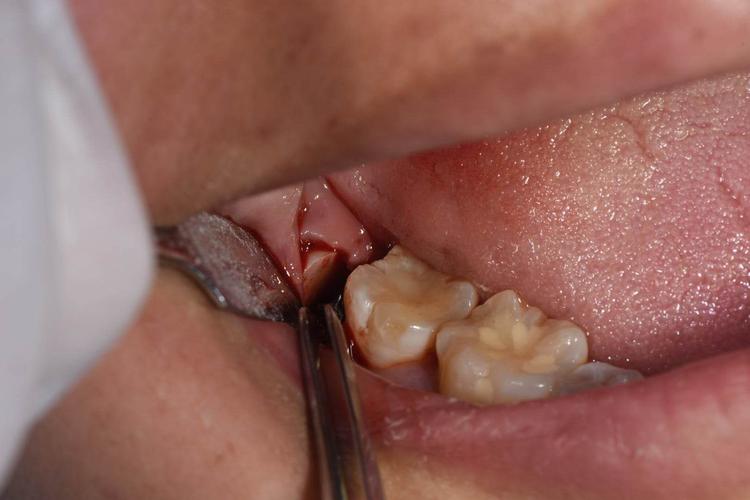

1、手术后的恢复时间

拔牙手术后的恢复时间因个体差异而有所不同,一般需要7-10天左右。在这个期间,患者需要注意休息,避免剧烈运动和咀嚼硬物,以免引发并发症。适当的饮食和口腔清洁也是恢复的关键。